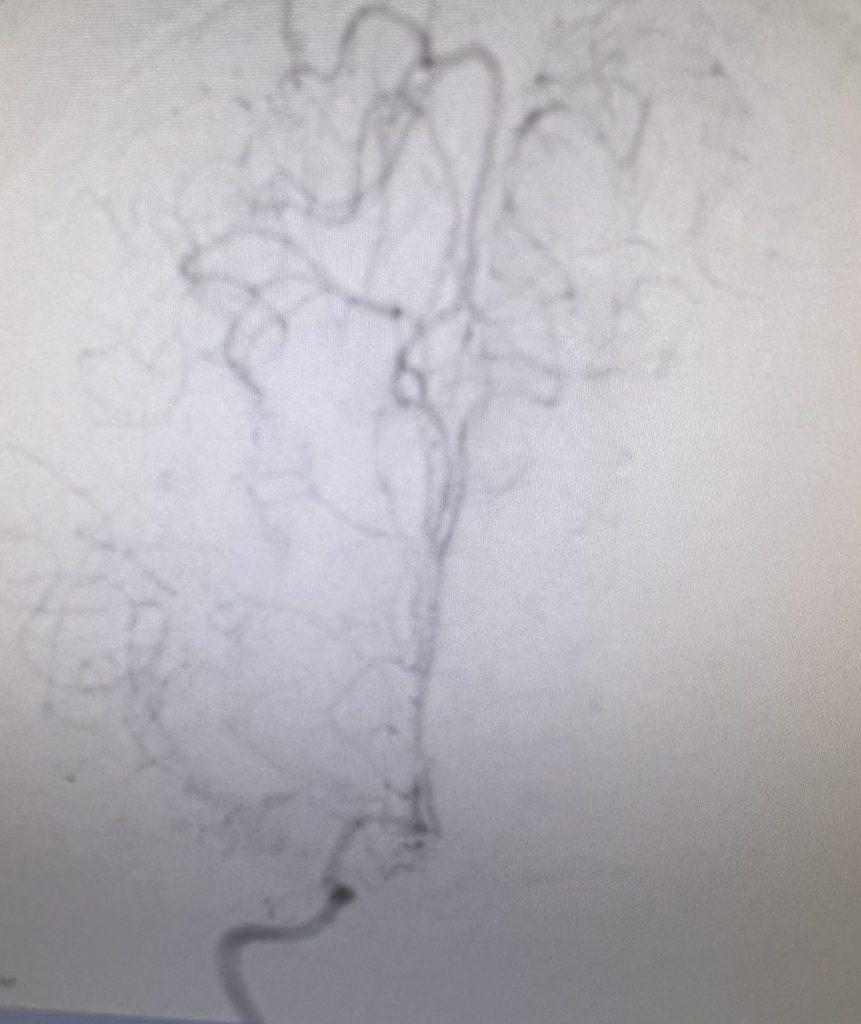

A right sided Encephaloduroarteriosynagios (EDAS) procedure was undertaken in which the right superficial temporal artery (STA) is sewn (synangiosed) to the pia in an effort to generate vascular arborization and increased blood flow to the hemisphere (Figure 3).

The surgery was uneventful, and the patient was restarted on her aspirin one day later and discharged home on postoperative day #2 neurologically intact.